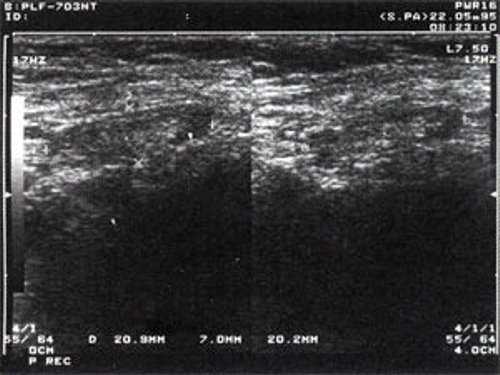

Практически во всех случаях дифференцировали лимфатический узел Кютнера (югулодигастральный), расположенный на границе средней и верхней трети шеи. Выявляемые лимфатические узлы имели размеры от 0,5 х 0,2 см до 2,3 х 0,8 см. УЗ-оценку производили после полипозиционного осмотра и нахождения самой длинной горизонтальной оси, что и принимали за максимальный поперечный диаметр. Большая часть лимфатических узлов (187) имели овальную форму с соотношением поперечного/переднезаднего более 1 (рис. 1 - 3). Тенденцию к округлению имели 30 лимфатических узлов, соотношение поперечного/переднезаднего приближалось к 1.

Рис. 1. УЗ-томограмма увеличенного реактивно измененного лимфатического узла: а - на фоне аденовирусной инфекции, б - после проведения противовоспалительного лечения

Рис. 2. Эхографическое изображение непальпируемого югулярного лимфатического узла на фоне остаточных явлений после перенесенного фарингита.

Рис. 3. Эхографическое изображение непальпируемого югулярного лимфатического узла без четкой клинической симптоматики воспалительного процесса в области головы и шеи.

Мы установили, что, как правило, более округлая конфигурация лимфатического узла при его размерах, превышавших 10 мм, сопровождалась небольшими болевыми ощущениями, и более выраженной простудной (воспалительного характера) симптоматикой. Лимфатические узлы менее 10 мм чаще всего плохо пальпировались, либо вообще не выявлялись пальпаторно. Во всех случаях эхографически хорошо дифференцировался гипоэхогенный кортикальный слой и широкое, средней или чуть ниже средней эхогенности изображение области ворот лимфатических узлов. Четкость дифференциации составных частей лимфатического узла была снижена при размерах менее 5 мм. Мы отмечали различную толщину гипоэхогенного изображения области коры лимфатического узла: от очень широкой - при выраженности или прогрессировании воспалительного процесса, до узкой - на фоне положительной динамики.